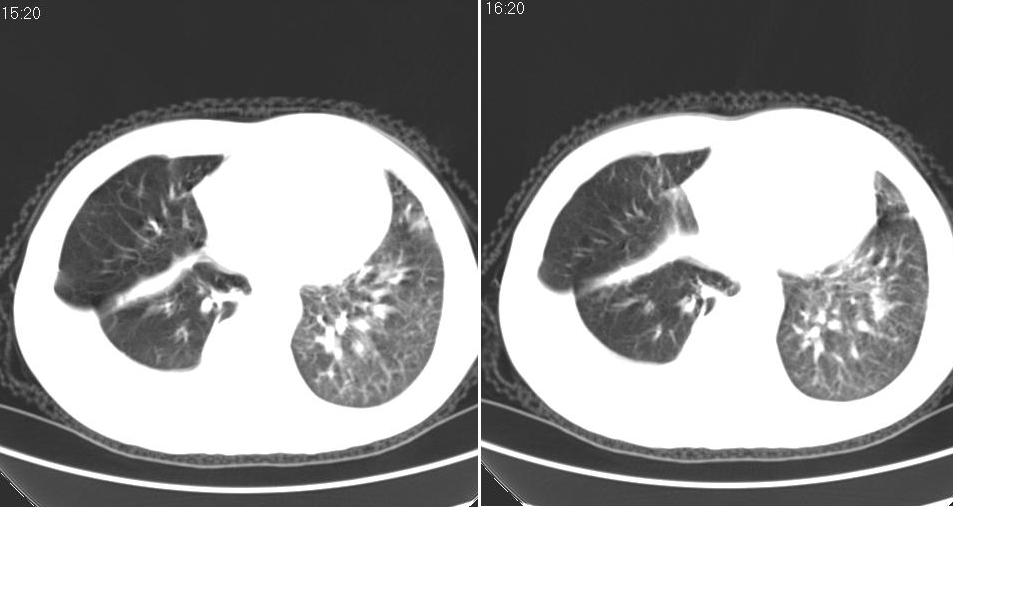

男 61岁,已确诊肺癌半年余.

考虑:1、右肺下叶中心型肺癌并纵隔淋巴结转移。胸腔积液。

2、心包少量积液。

3、左肺改变不除外癌性淋巴管炎或化疗后肺间质纤维化。

1 右肺下叶中心型肺癌.纵隔内淋巴结转移.右侧胸腔积液. 2 心包少量积液.3 肺间性改变考虑与化疗有关.

补充一下:右肺底好象有一个类圆形的结节影,可考虑为肺部转移。如图示。[

考虑:1、右肺下叶中心型肺癌并纵隔及左肺门淋巴结转移。胸腔积液。

3、左肺改变与左肺门肿大淋巴结影压迫主支气管有关。